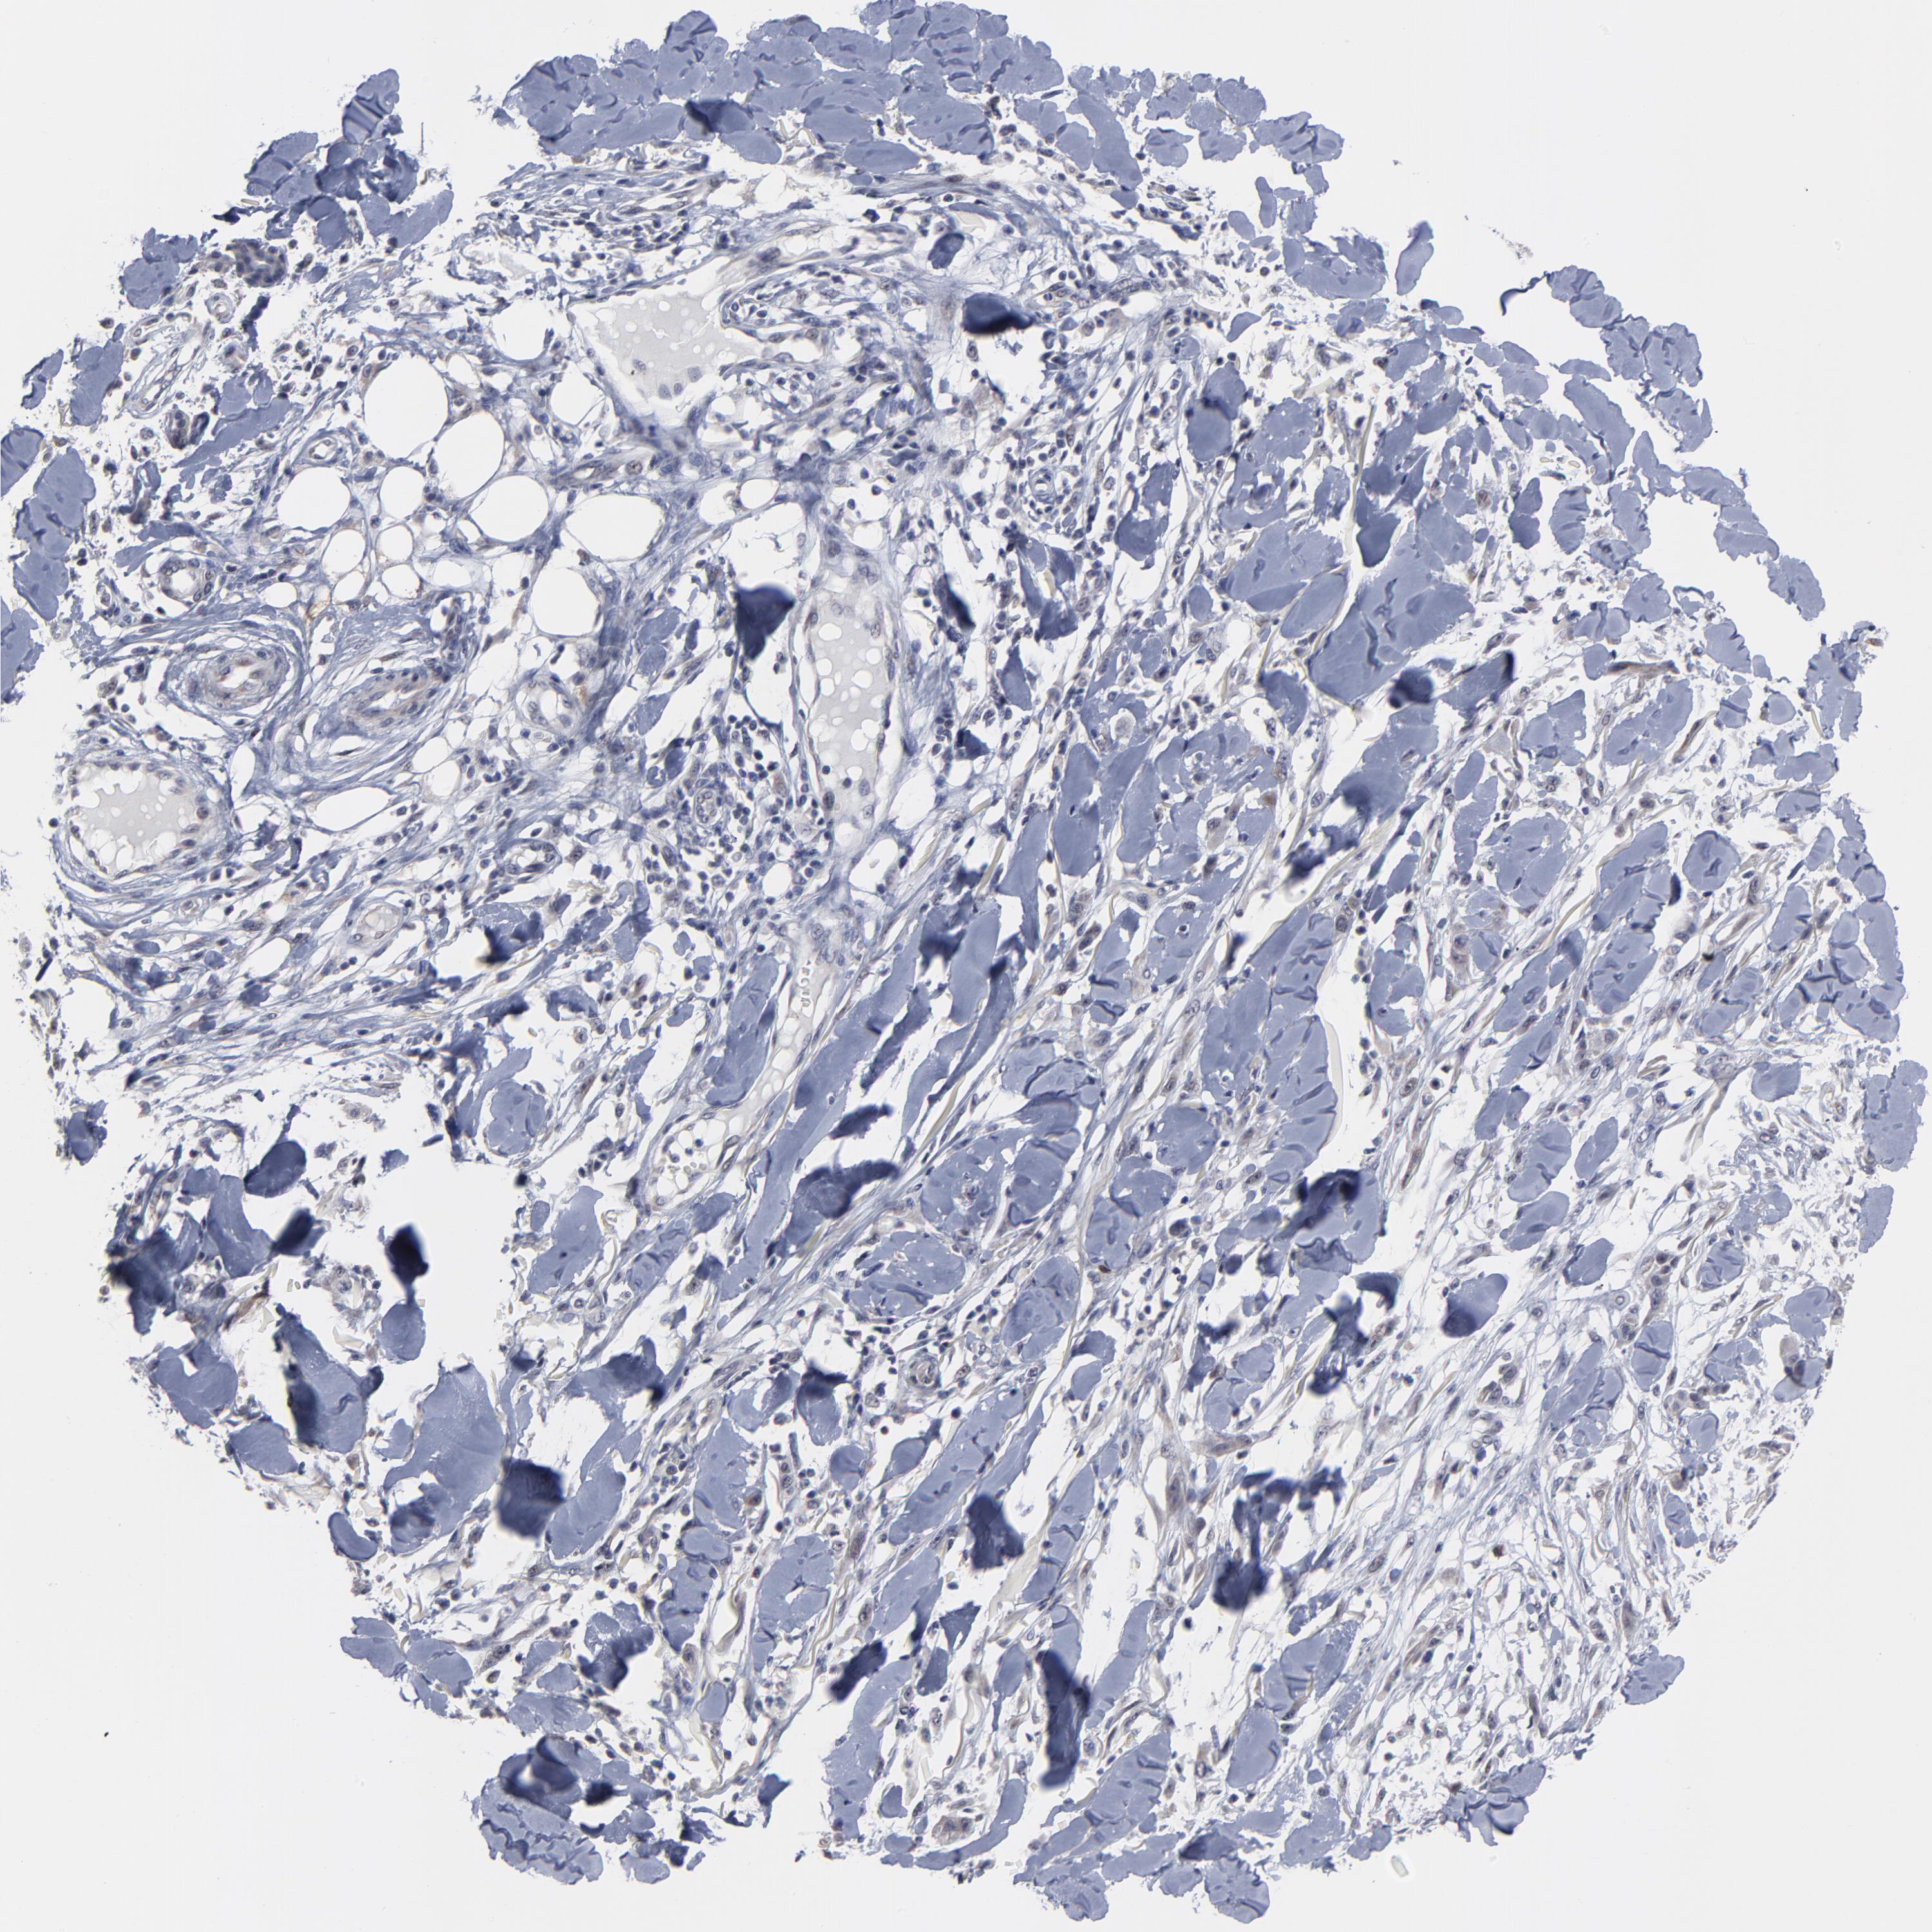

SKIN CANCER - Protein expressioni

A mouse-over function shows sample information and annotation data. Click on an image to view it in a full screen mode. Samples can be filtered based on level of antibody staining by selecting one or several of the following categories: high, medium, low and not detected. The assay and annotation is described here.

Antibody stainingi

Antibody staining in the annotated cell types in the current human tissue is reported as not detected, low, medium, or high, based on conventional immunohistochemistry profiling in selected tissues. This score is based on the combination of the staining intensity and fraction of stained cells.

Each image is clickable and will lead to virtual microscopy that enables deeper exploration of all samples and also displays staining intensity scores, fraction scores and subcellular localization as well as patient and tissue information for each sample.

Antibody HPA003333

Squamous cell carcinoma, NOS

Basal cell carcinoma